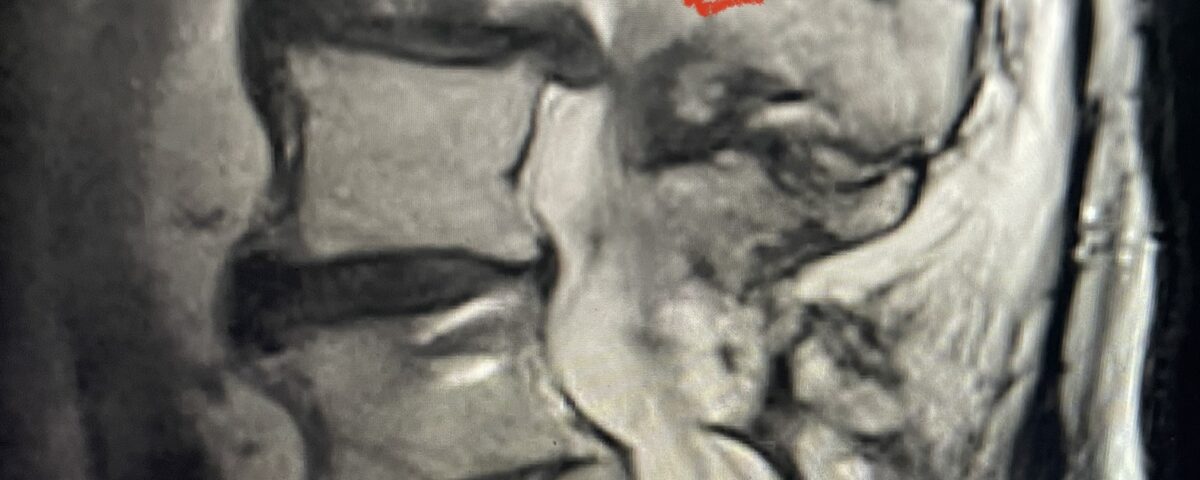

The patient had failed all means of conservative management including Physical Therapy and epidurals. He had an extensive medical history including stroke, cardiac stents, diabetes on insulin, hypertension, hypercholesterolemia, and kidney disease. Since he had a prior fusion with instrumentation for L4-S1, it was interesting that the patient had not developed significant next segment stenosis at L3-4. However, CT analysis (Fig. 2) demonstrated a partial fusion that extended from L3 to L4 which prevented abnormal motion.

Fig 2: Coronal lumbar CT demonstrating L4-S1 fusion with instrumentation with some incomplete bony fusion to the L3-4 segment (red arrow)